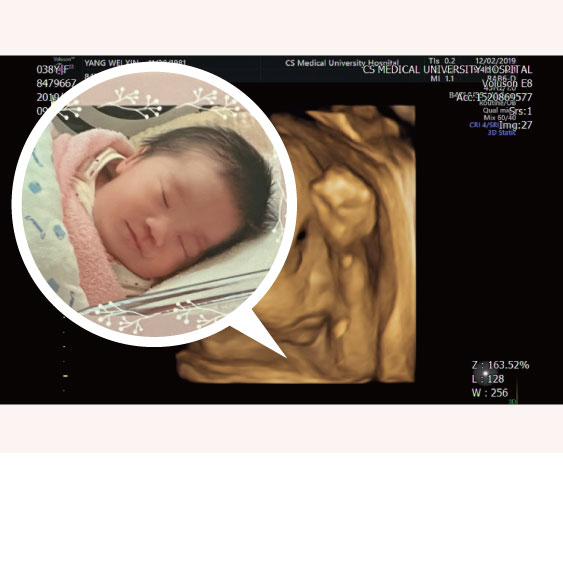

MIRA找出妳的植入時程 2023-12-28

婚後懷孕未果 著床時間異於常人

夫妻婚後未孕且AMH值低,利用MIRA檢測子宮內膜狀態,發現著床時間異於常人,調整後成功生下女寶寶。祝福新手爸媽